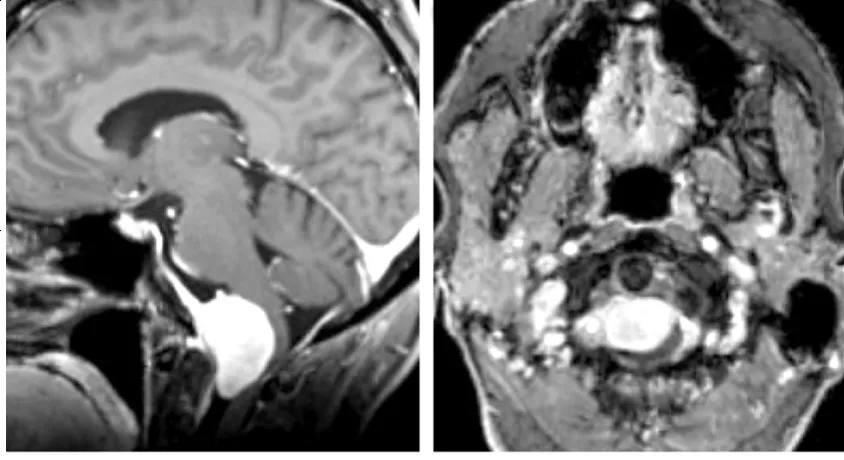

MRI是目前确诊枕骨大孔区脑膜瘤的重要手段。T1加权像多呈等信号或略低信号,T2加权像为等信号或高信号,部分病例可见囊变坏死、出血征象,肿瘤边界大多清晰。静脉注射钆造影剂增强扫描后,肿瘤呈现显著均匀强化,大部分病例可见典型"脑膜尾征"。

同时,MRI矢状位和冠状位图像可直接显示延髓、颈髓受压情况。当肿瘤侵犯脑干软脑膜时,T2加权像可见脑干区域高信号改变,FLAIR像表现更为明显,这常提示脑水肿存在,肿瘤压迫脑干导致水肿往往影响肿瘤切除程度及术后并发症发生。增强结果可反映肿瘤血供情况,轴位及冠状位图像也有助于判断肿瘤与同侧椎动脉及周边硬脑膜的关系。MRI也是鉴别枕骨大孔区肿瘤与颈椎病、寰枕畸形等重要手段。

图示:典型枕骨大孔腹侧脑膜瘤,伴沿斜坡走行的鼠尾征(上图),肿瘤常侵犯颈静脉孔增加手术难度,需采用远外侧入路切除肿瘤。